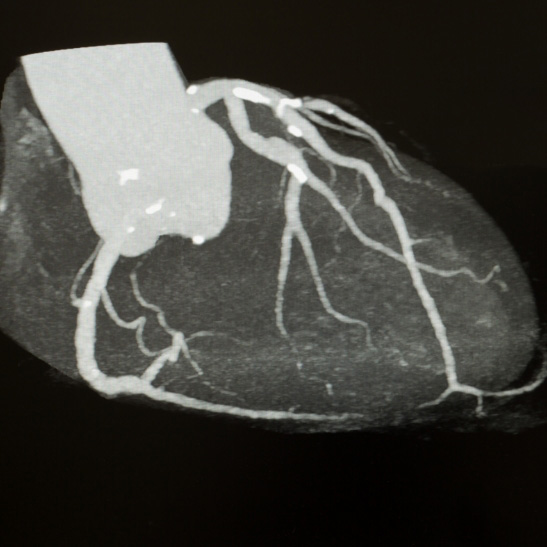

CT coronary angiogram

This uses X rays to provide information regarding the coronary arteries, and can identify calcium build up (hardening of the arteries) as well as any narrowings or blockages. This can be a very useful alternative to a conventional coronary angiogram.